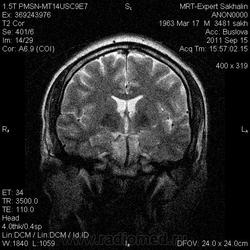

Глаз тигра?

Пациент с жалобами на головную боль.В направлении  дисциркуляторная энцефалопатия.

Первые 3 скана и есть флайер.Не только область базальных ядер ,но левая височная область.

Извиняюсь не распознала флаер. В области полюса левой височной доли арахноидальная киста. Признаков масс- эффекта не вижу. Что касается базальных ядер не уверена что это есть патология. Но еще посмотрю подумаю.

Уж больно бросается в глаза симметричный пониженный сигнал от подкорковых образований. Я так понимаю вы пытаетесь исключить болезнь галлервордена- шпатца?

симметричная дегенрация подкорковых ядер -отложение депозитов железа.